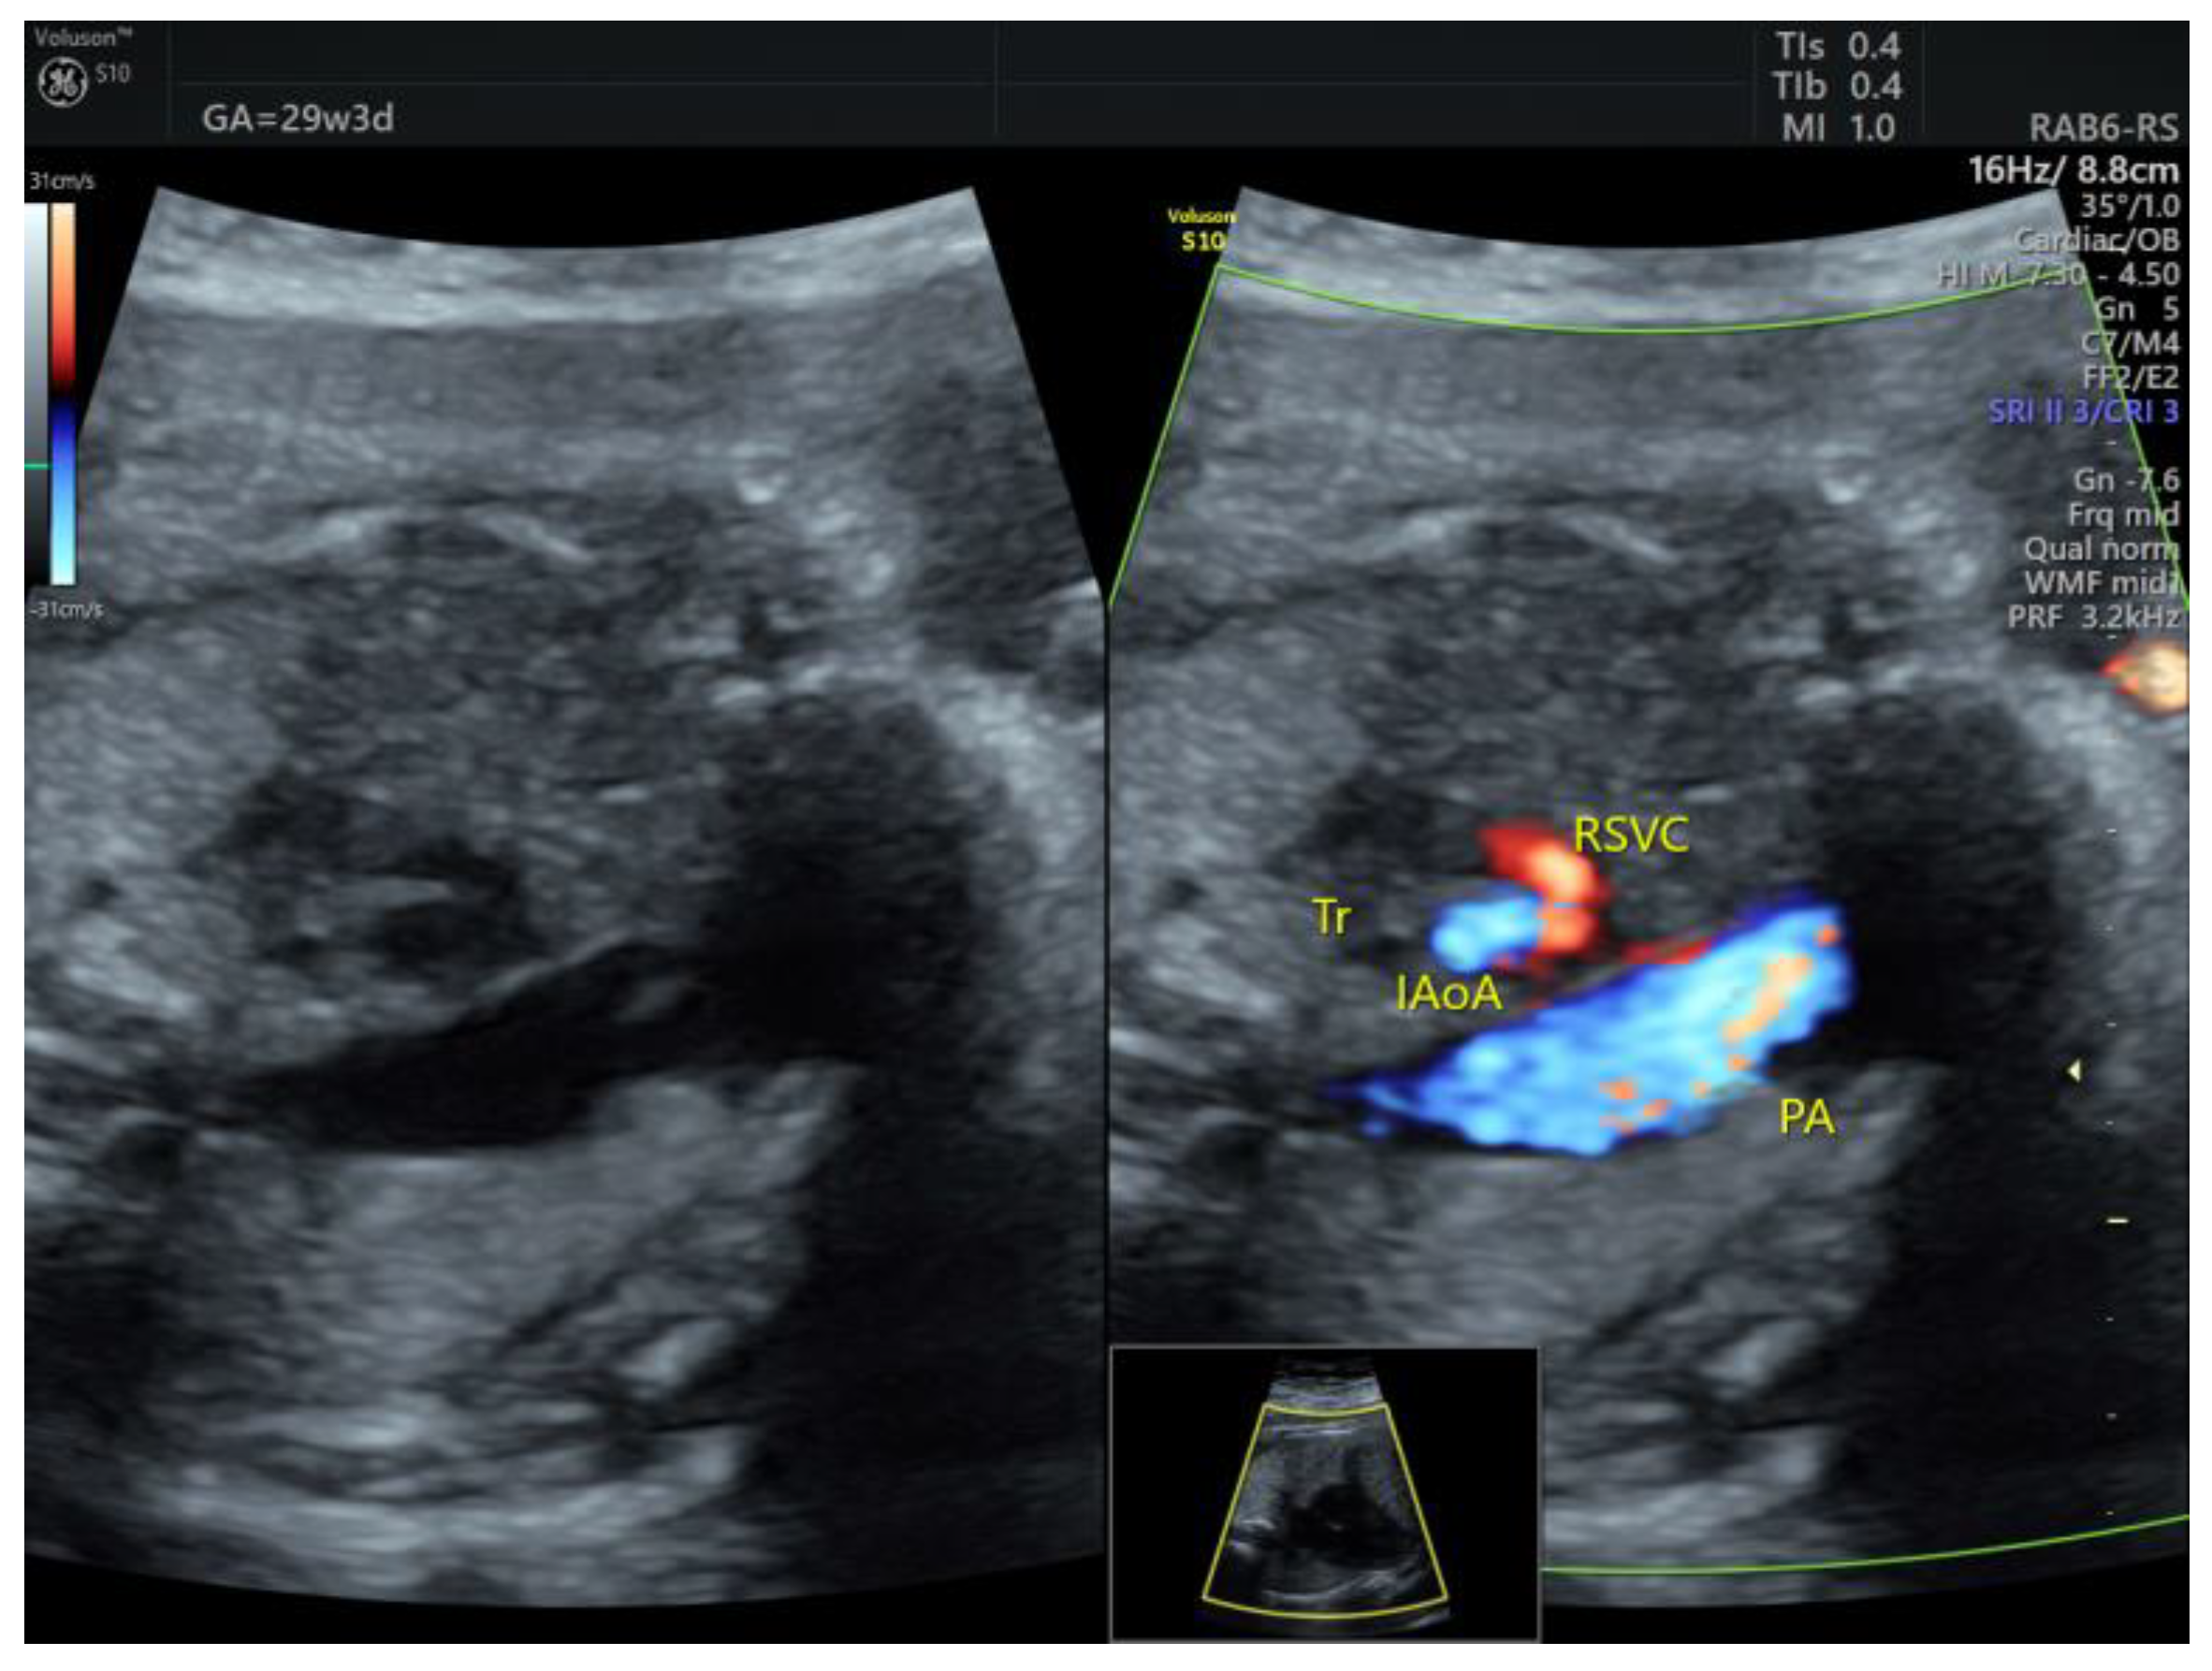

| IAoA | 1 | perimembranous VSD | - | 3VT | + | 0 | 1 | 0 | 1/1 |